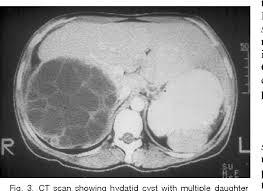

Daughter cysts

Echinococcal cyst within a larger cyst

Can occur in liver or spleen